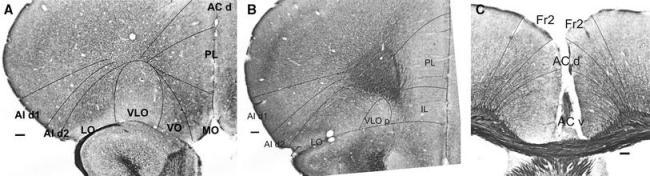

Cytoarchitectonic and chemoarchitectonic characterization of the prefrontal cortical areas in the mouse.

This study describes cytoarchitectonic criteria to define the prefrontal cortical areas in the mouse brain (C57BL/6 strain). Currently, well-illustrated mouse brain stereotaxic atlases are available, which, however, do not provide a description of the distinctive cytoarchitectonic characteristics of individual prefrontal areas. Such a description is of importance for stereological, neuronal tracing, and physiological, molecular and neuroimaging studies in which a precise parcellation of the prefrontal cortex (PFC) is required. The present study describes and illustrates: the medial prefrontal areas, i.e., the infralimbic, prelimbic, dorsal and ventral anterior cingulate and Fr2 area; areas of the lateral PFC, i.e., the dorsal agranular insular cortical areas and areas of the ventral PFC, i.e., the lateral, ventrolateral, ventral and medial orbital areas. Each cytoarchitectonically defined boundary is corroborated by one or more chemoarchitectonic stainings, i.e., acetylcholine esterase, SMI32, SMI311, dopamine, parvalbumin, calbindin and myelin staining.